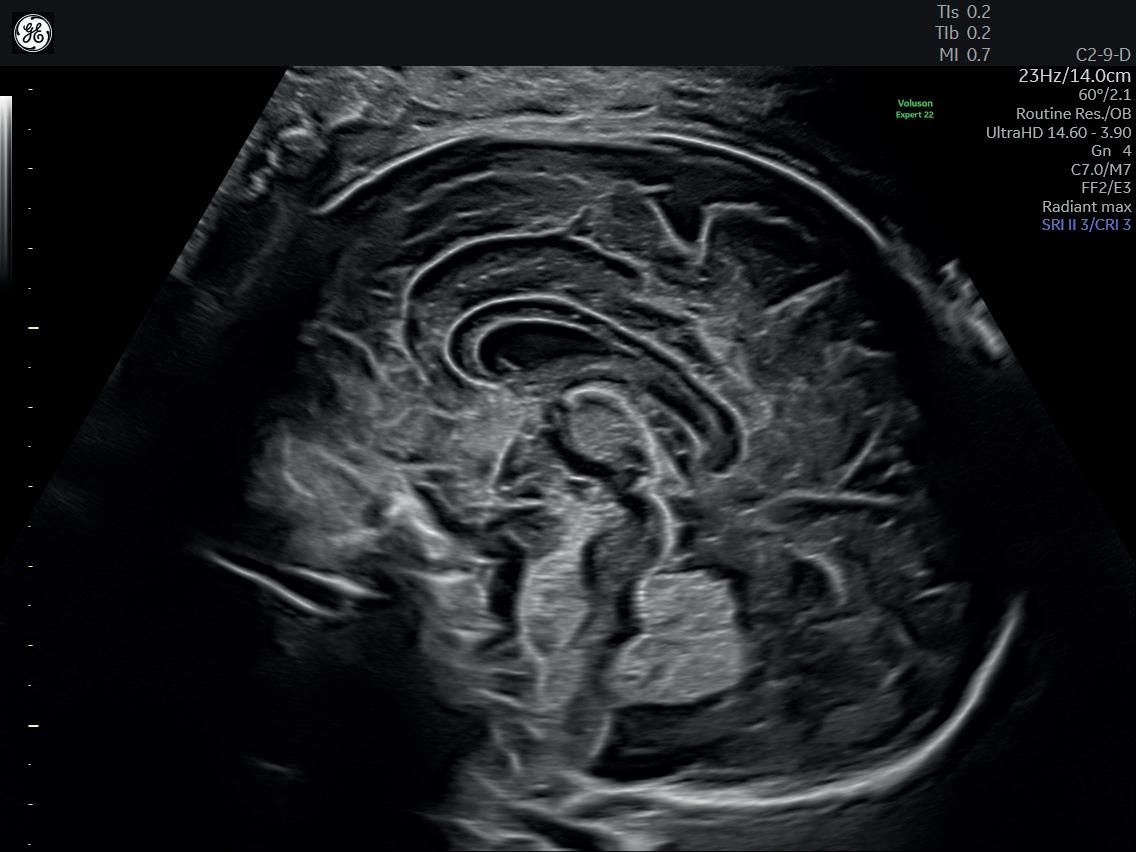

τμήματος Fetal Medicine, υπό την εποπτεία του καθηγητή Κύπρου Νικολαϊδη στο King’s College Hospital. Από το 2000 και για δύο χρόνια, προσέφερε τις υπηρεσίες της στο Αρεταίειο Νοσοκομείο Αθηνών, καθώς συμμετείχε στις δραστηριότητες του Τμήματος Υπερήχων και Εμβρυομητρικής Ιατρικής και στις δραστηριότητες της Β’ Μαιευτικής-Γυναικολογικής Κλινικής Πανεπιστημίου Αθηνών. Στο ίδιο νοσοκομείο και για τα έτη 2003-2006 εργάστηκε ως Επιστημονικός Συνεργάτης στο Τμήμα Υπερήχων και Εμβρυομητρικής Ιατρικής της Β’ Μαιευτικής και Γυναικολογικής Κλινικής του Πανεπιστημίου Αθηνών. Από το 2023 είναι Clinical Instructor του Nicosia University.